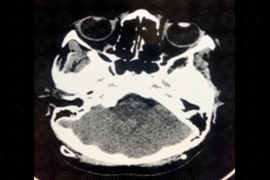

Descrição das imagens: Tomografia computadorizada do plano axial, exibindo a fossa posterior pequena e interdigitação da foice cerebral. Achados compatíveis com malformação de Chiari tipo 2. Observa-se ainda a presença de cateter de derivação ventricular na região parietal posterior esquerda.

• Tomografia computadorizada do crânio: Fossa posterior obliterada (pequena), incisura do tentório alargada, mesencéfalo em bico e deslocamento inferior do vérmis cerebelar;